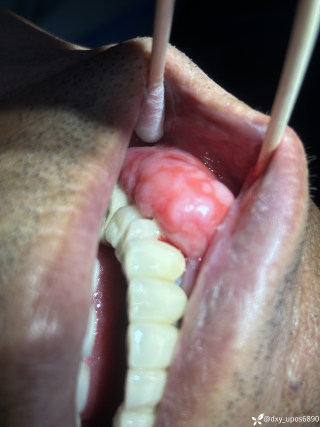

反思 | 赶高铁时一过性晕厥的老年男性

月叔打怪兽急诊科医师

昨天值班遇到的一例晕厥病例,差点漏诊,而最终的解法,始于最简单而质朴的查体。国庆中秋双节的最后一天,8号的早上8点,抢救室床旁晨交班,病人依旧是多而重,交到6床,一个刚入室不久的病人,准备去做CT,夜班医师汇报病史:69岁男性,本次因“头晕伴一过性晕厥1小时”为主诉入抢,1小时前于高铁站因即将赶不上高铁走路快时突发头晕,伴一过性晕厥,约3-4分钟后清醒,清醒后诉今晨未吃早餐,已服用降压药物,仍有头晕头痛、四肢乏力等不适,无胸闷胸痛,无畏寒发热,无咳嗽咳痰,无恶心呕吐,无肢体麻木,无视物模糊等不适,路人拨打120送至我院急诊就诊。既往高血压,长期服用氨氯地平+福辛普利,血压控制一般;糖尿病,长期